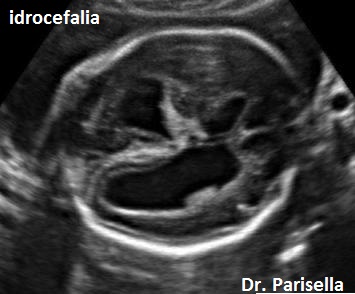

Ecograficamente si caratterizza per la presenza di  ipoplasia del corpo calloso, anomalie di struttura dei pollici (pollici addotti), idrocefalia lieve o moderata.